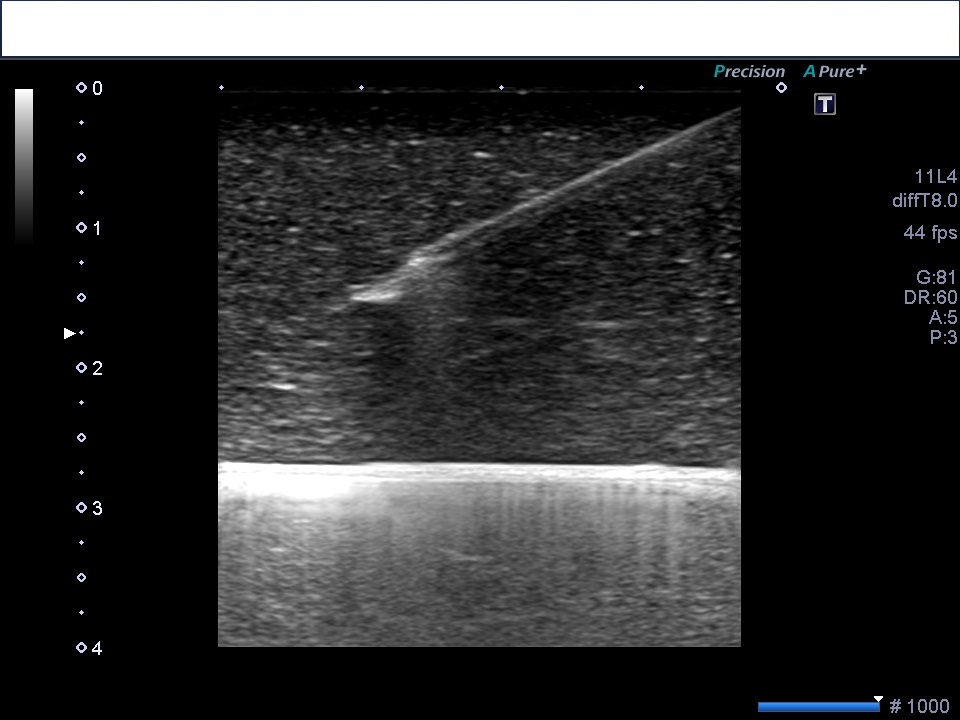

【長軸穿刺】

こんにゃくを使用した練習穿刺です。こんにゃくの種類でエコー画像が違います。内部が粗くとても見にくいこんにゃくもあるので購入時に数種類検討してみてください。

空気や液体を注入してどのような画像になるか見たり、針の角度がどれくらいで刺すとどこの深さになるのか、自分には縦走査の穿刺が向いてるのか、横走査の穿刺が向いてるのか等、再確認できます。

長軸穿刺ではプロ―ブの中心がエコーでの画像描出部位になるので、黒の点線上に針が通るような向きで穿刺すると画像に穿刺針が映ります。穿刺位置は中央なのに向きが中心上を通ってないと画像で見ることはできません。

また、プローブを持つ人は、プローブが徐々にずれないように、患者と持ち手の一部をくっつけておくといいです。私は小指をくっつけてます。こんにゃくもよく滑るので同じ位置での固定は難しいです笑

プローブのすぐ近くから穿刺してしまうと、針で皮膚の表面が押され、穿刺時にエコーの画像が押された皮膚の部分だけ見れなくなります。少し離した位置で穿刺するとエコー画像は欠如しなくて済みます。

穿刺時、静脈の前壁 が押されたように見え静脈は変形します。針が前壁を貫くと形状が戻るので血管内に入ったのがわかります。

GWを挿入するとき、針先と後壁との間に距離が必要でGWが後壁に当たり挿入しにくい時があります。穿刺針をほんの少し引いて持ち上げるようにすると挿入しやすくなります。

慣れるまで、長軸穿刺のほうが確実な印象があります。